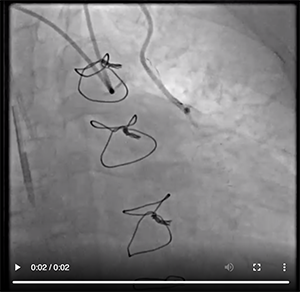

Because the aortic arch was mildly calcified and only mildly tortuous, we were able to negotiate the left subclavian artery with relative ease using a 0.035-inch angled Glidewire Advantage guidewire (Figure 1). Because the patient developed spasm, we chose not to exchange to another catheter and used the JR 4 catheter for the native right coronary artery (Figure 2) and all the grafts, including the LIMA. There was clear diffuse disease progression in the native LAD artery. We discussed intensifying medical therapy and more aggressive dialysis to stabilize her LV function, but we decided against it due to changes in the electrocardiogram and spasm. Video 1 and Video 2 reveal the anatomy defined during catheterization. Video 3, Video 4, and Video 5 illustrate how we negotiated the left subclavian artery and the subselective LIMA angiogram.